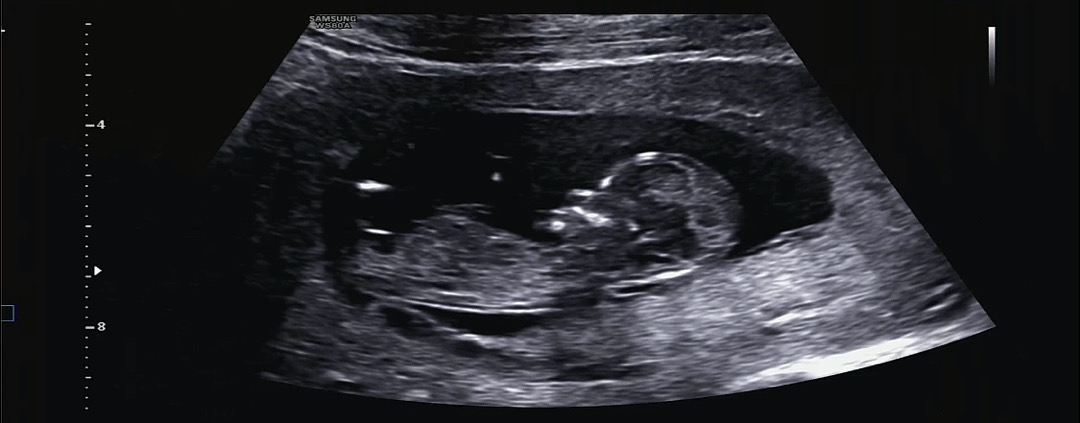

12주 1일 각도법

아들일까요 딸일까요? ꒰ ⸝⸝ɞ̴̶̷ ·̮ ɞ̴̶̷⸝⸝꒱

촘파가 잘 안보이긴하지만 아들한표용!